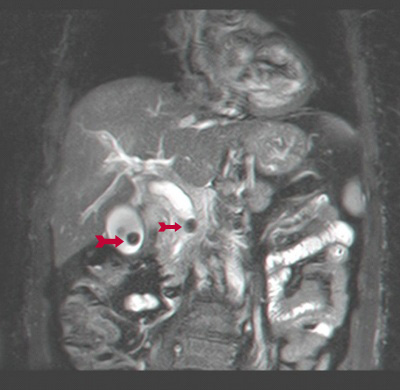

ה- MRCP היא בדיקה אמינה מאוד לגילוי פתולוגיות בדרכי המרה ואבני מרה (תצלום 29.8) והמהלך האנטומי של דרכי המרה.

Endoscopic retrograde cholangio pancreatography (ERCP) בשיטה זו מחדירים אנדוסקופ דרך הפה לתריסריון, מזהים את הפפילה על-שם ואטר, ולתוכה מחדירים צנתר שדרכו מזריקים חומר ניגוד לדרכי המרה וללבלב. ההדגמה היא רנטגנית וניתן לראות בה הרחבה של דרכי המרה, אבנים בדרכי המרה (תצלום 30.8) ועוד.